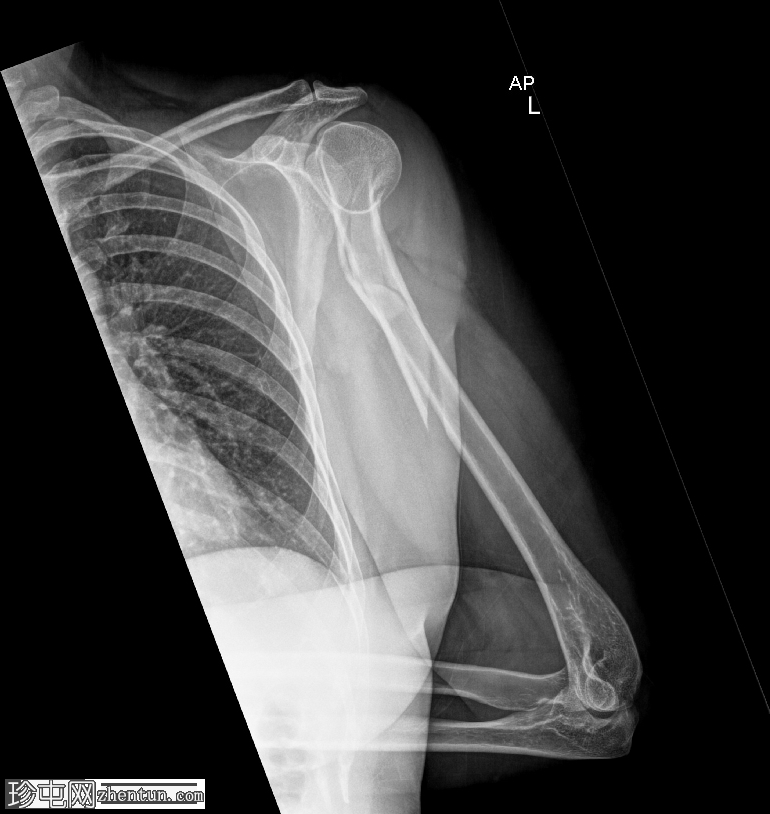

斜位

肱骨近端粉碎性移位骨折,累及骨干近端半部、外科颈,并延伸至大结节。

肱骨头在肩关节内向下半脱位,肩峰肱骨间距增大。

肱骨头向下移位(假性半脱位)是肱骨近端骨折常见的继发性表现。它提示关节积液、关节积血或暂时性关节囊松弛,而非肩关节真正的不稳。手臂负重和肌肉张力下降(尤其是三角肌和肩袖肌群)共同导致肱骨头相对于肩胛盂位置下移<sup>1-3</sup>。

这种表现不应与真正的肩关节脱位混淆,因为在Y形位或轴位影像上,肱骨头仍与肩胛盂保持正确的对位。随着关节液的吸收和肌肉张力的恢复,这种情况通常会自行缓解。识别这种暂时性的良性表现对于避免不必要的复位手术至关重要。

在本病例中,肱骨头位置下移反映了由急性近端肱骨骨折引起的关节积液所致的假性半脱位,而没有真正的脱位证据。